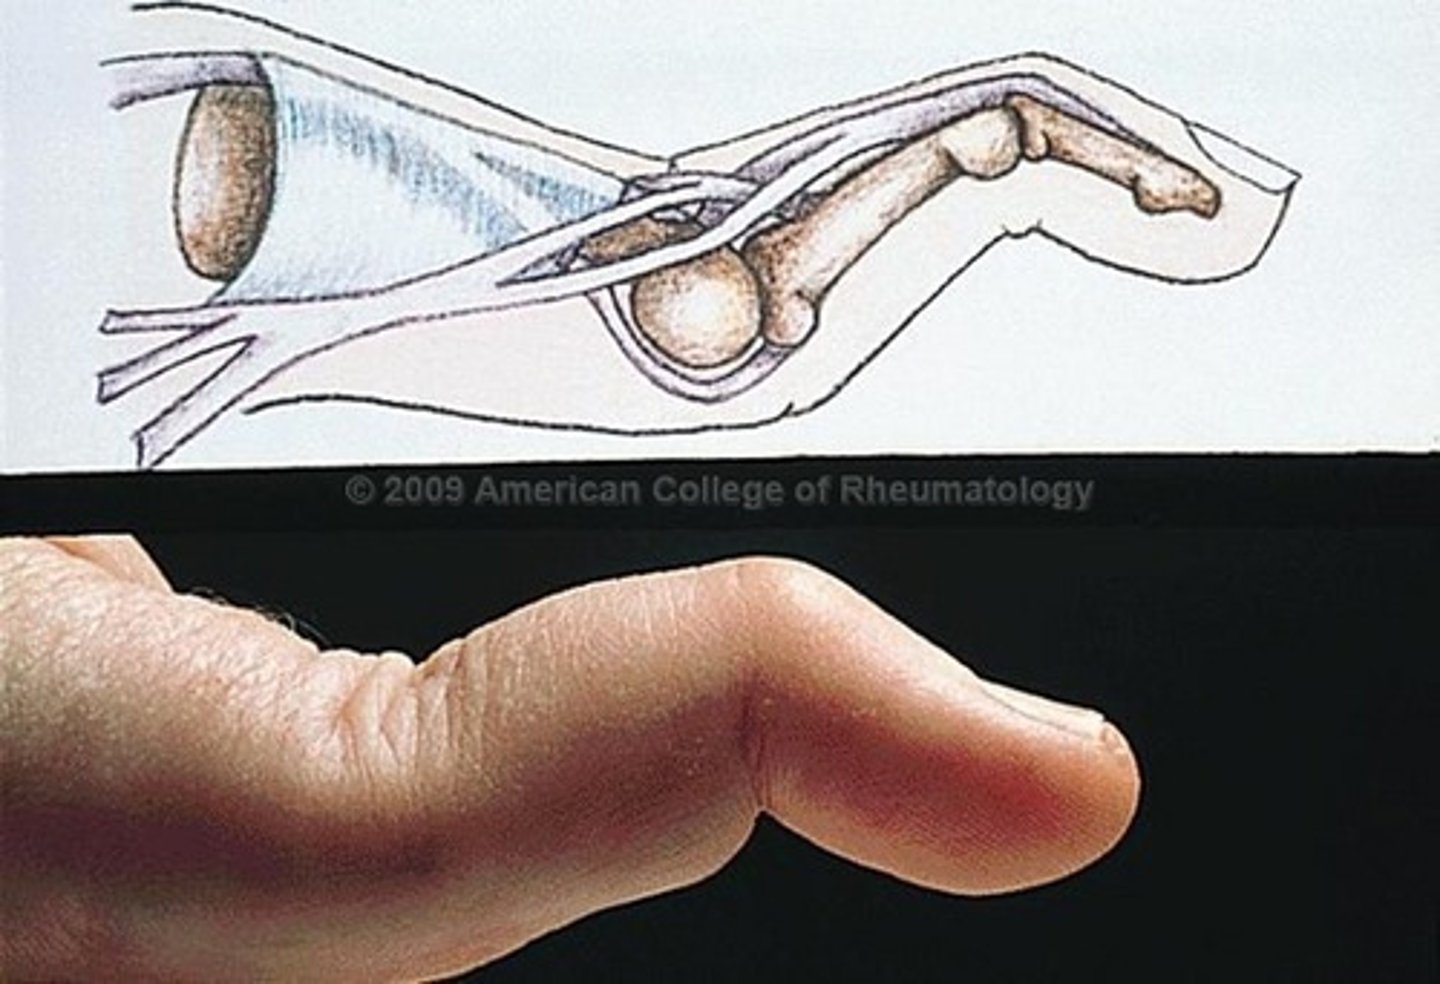

swan-neck deformity

hyperextension of PIP and flexion of DIP, characteristic of rheumatoid arthritis

Boutonniere deformity

flexion contracture of a PIP joint, extension of a DIP joint, characteristic of rheumatoid arthritis